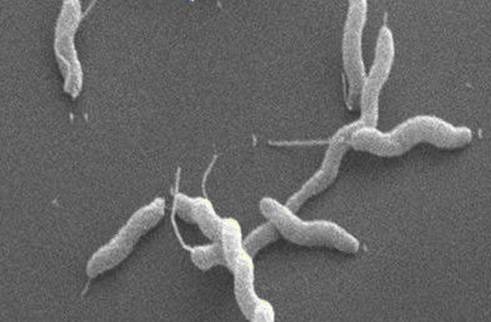

Кампилобактер фетус: патогенез и инфекции